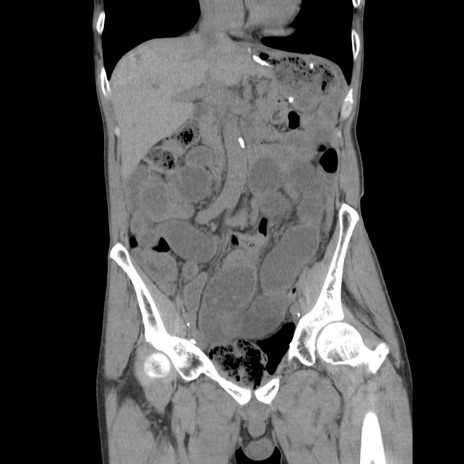

症例11(冠状断像)

【症例】 60歳代男性

【主訴】 下腹部痛

【現病歴】 本日夜中より下腹部痛の症状認め、受診。

【既往歴】 膀胱癌(膀胱全摘+尿管皮膚瘻術) 、胃癌術後

【身体所見】 BT 35.3℃、PR 58/min、BP 136/98mHg、腹部平坦、軟、腸蠕動音±、ストマ留置あり、左上腹部~正中部に圧痛あり、反跳痛なし。

【データ】WBC 5100、CRP0.01